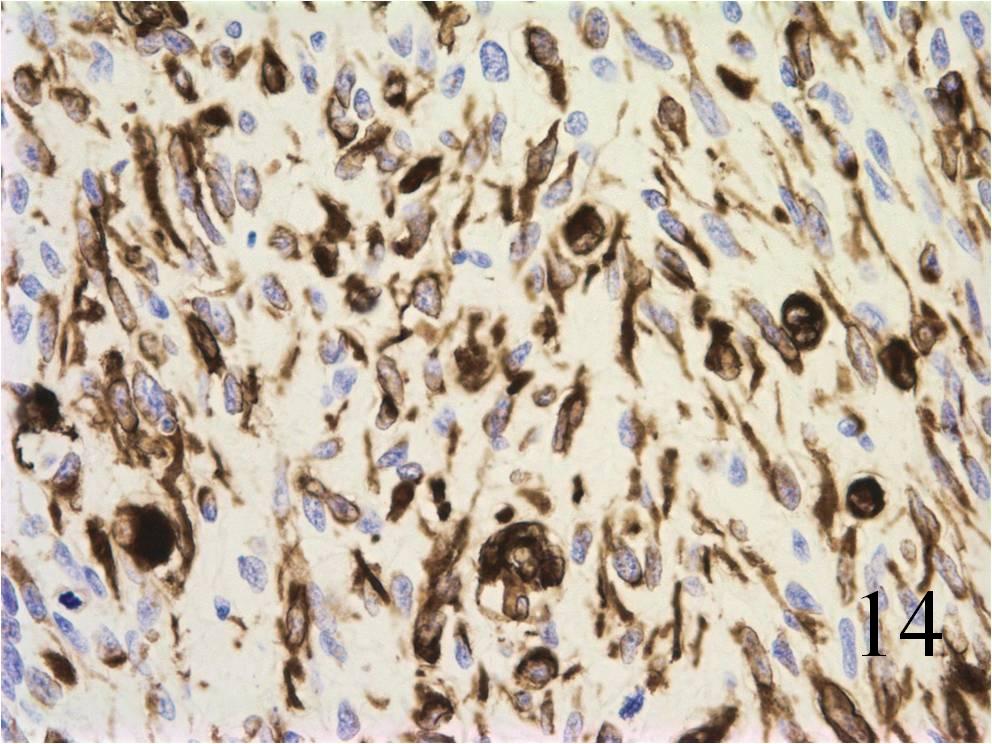

Immunohistochemistry

- Vimentin positive; Keratin negative

- Actin variable; perhaps minor scant staining

- S-100 negative

- Small round blue cells (Fig. 12-15)